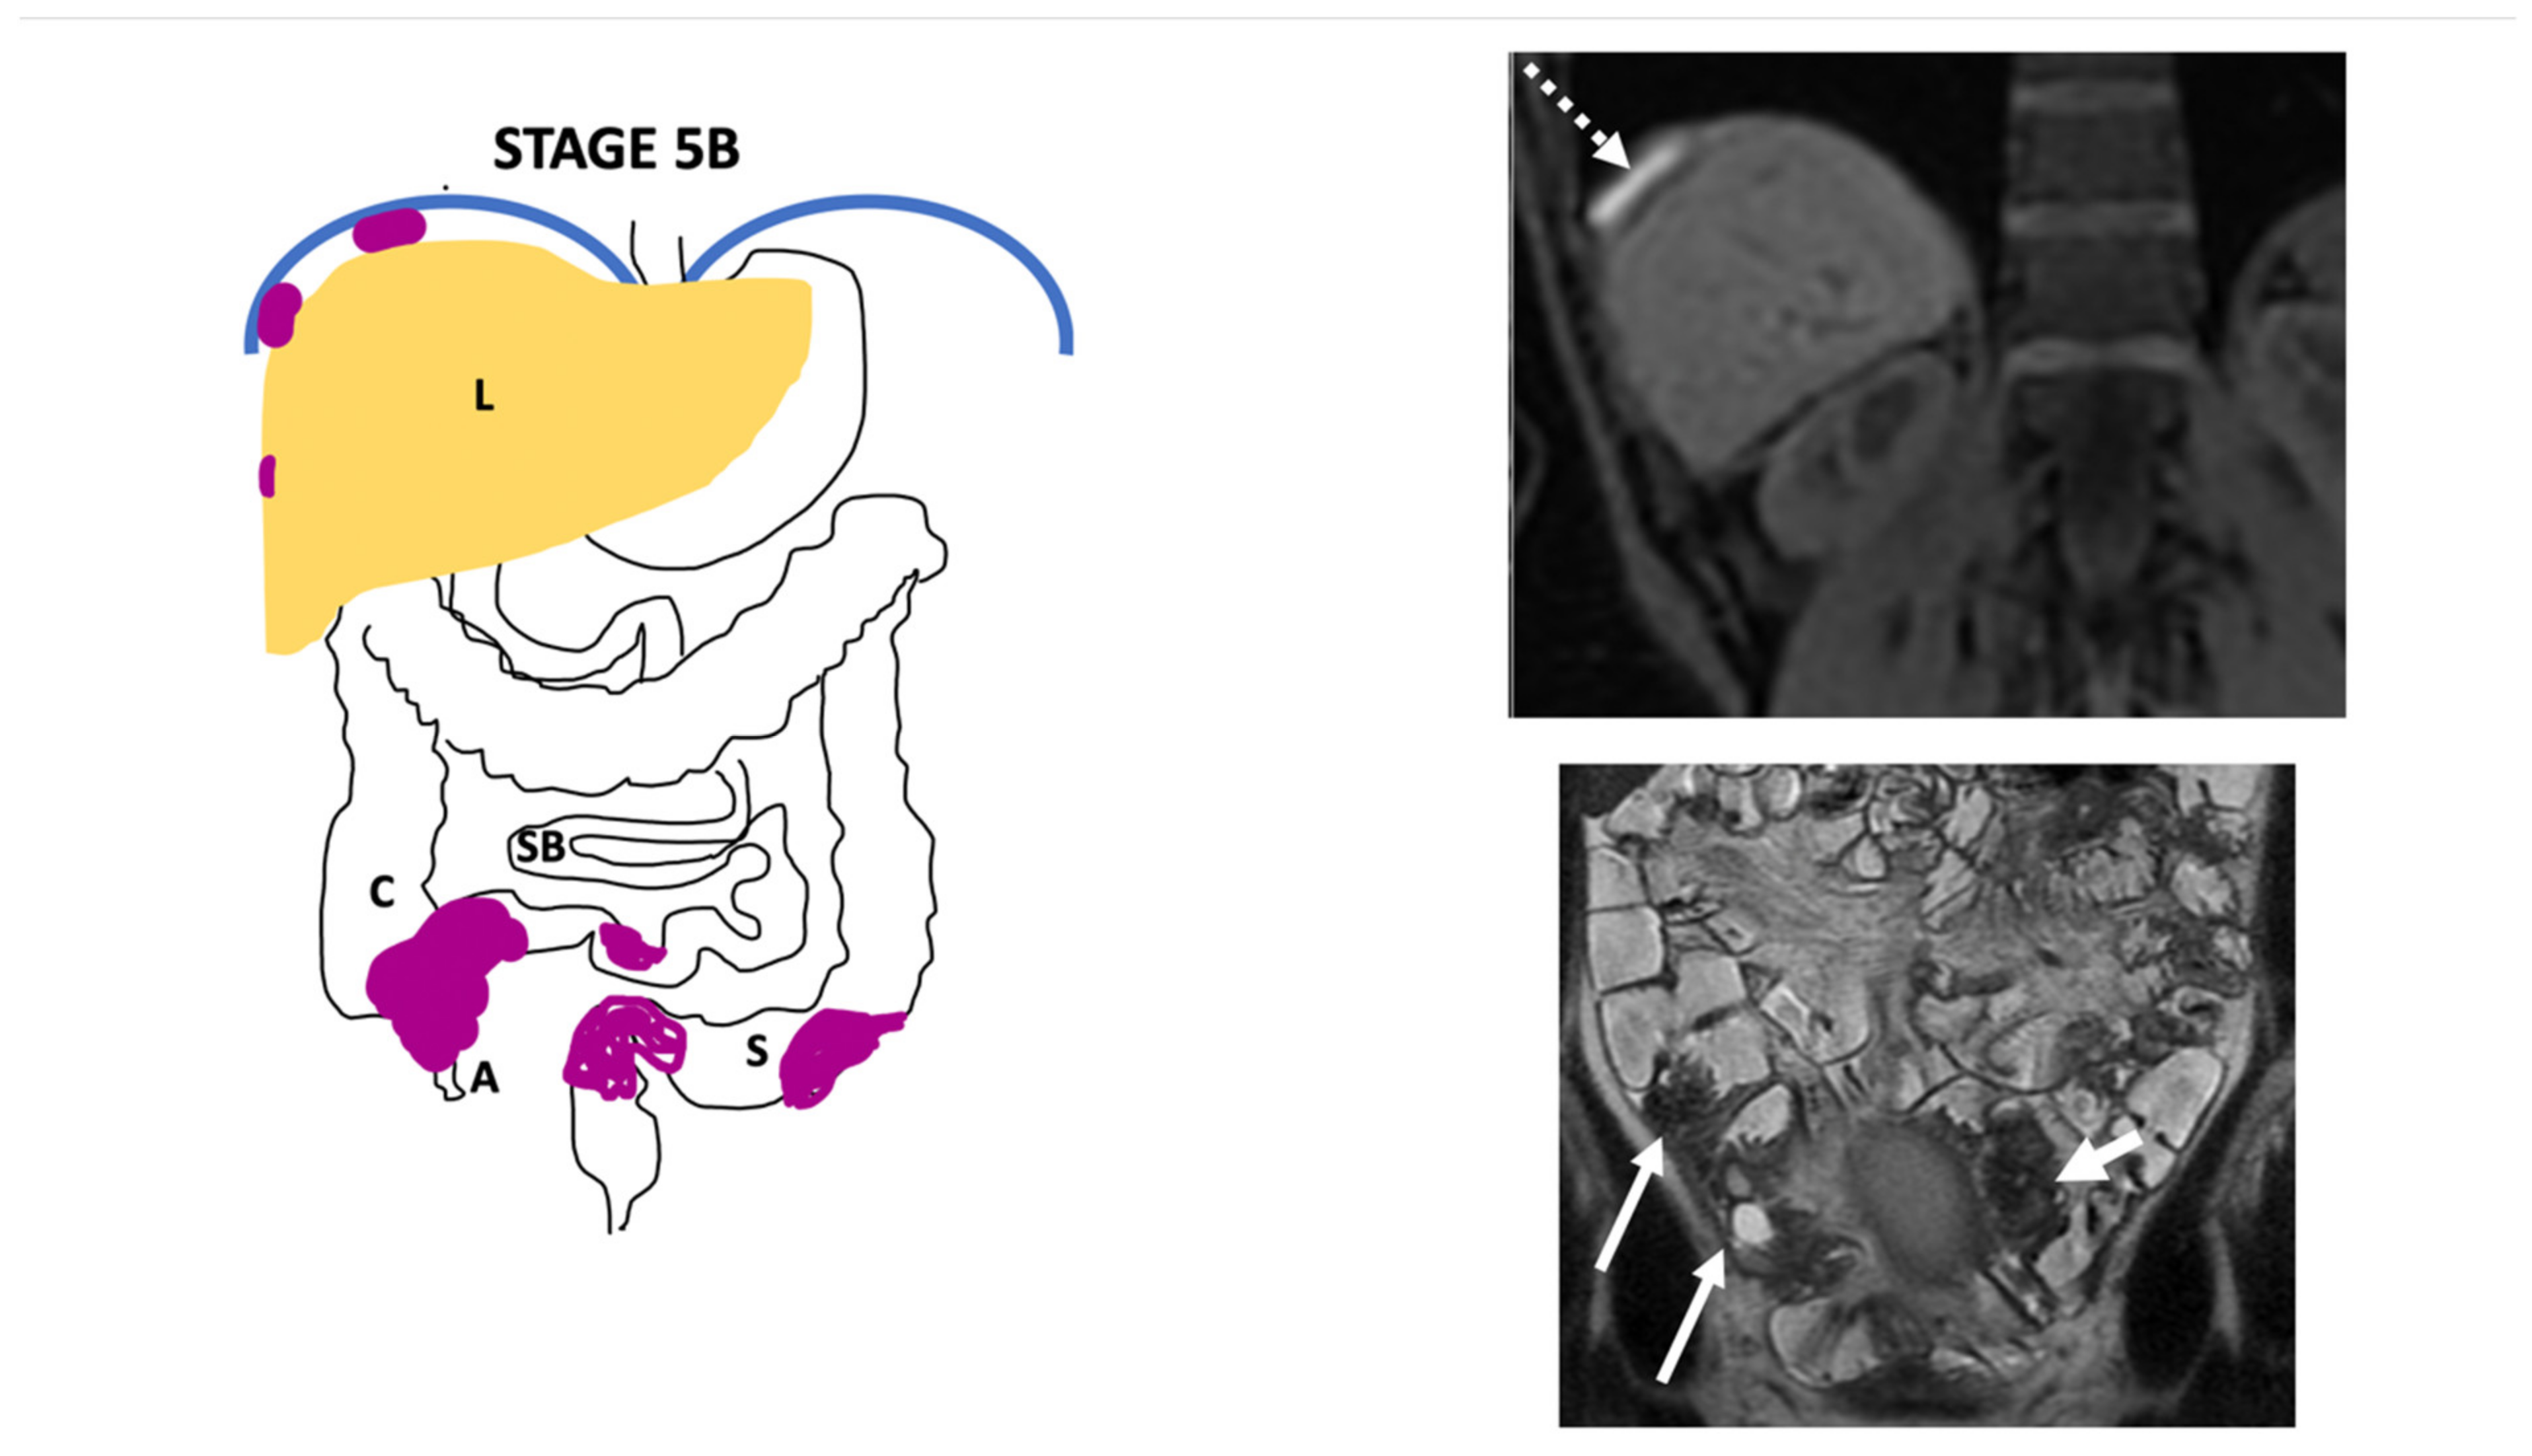

| Endo-Stage MRI 0 | Superficial endometriosis |

| Low |

| Endometriosis is strictly confined to the ovaries |

| ||

| Endo-Stage MRI I | Endometriosis is strictly confined to the retrocervical area |

| |

| Endo-Stage MRI II | Endometriosis invades beyond the retrocervical area, but not to the pelvic side-wall |

| Endo-Stage MRI III | Endometriosis extends to the pelvic side-wall and/or causes hydronephrosis or non-functioning kidney |

| Intermediate |

| Endo-Stage MRI IV | Endometriosis has involved the bladder or rectosigmoid colon |

| Endo-Stage MRI V | Multiple deep endometrioticlocations |

| High |